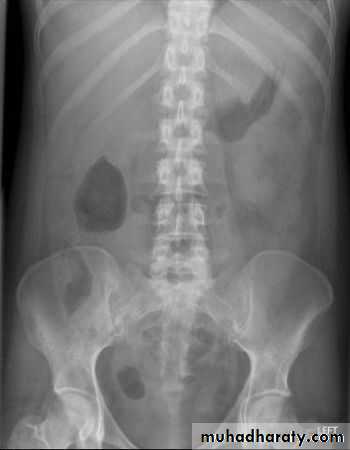

Ascites

Plain films are of very limited value in the diagnosis of ascites

Small amounts of ascites cannot be detected on plain films.

Larger quantities separate the loops of bowel and displace the ascending and descending colon from fat stripes. SB loops float to the center of abdomen

Ascites is more readily recognized with ultrasound or CT